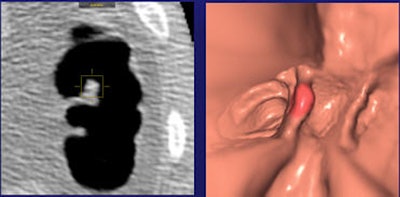

| In a 59-year-old man, a 6-mm sessile polyp on a haustral fold visible only on the prone scan was missed by the radiologist but found by CAD. Histology: hyperplastic. All images courtesy of Dr. Daniele Regge. |